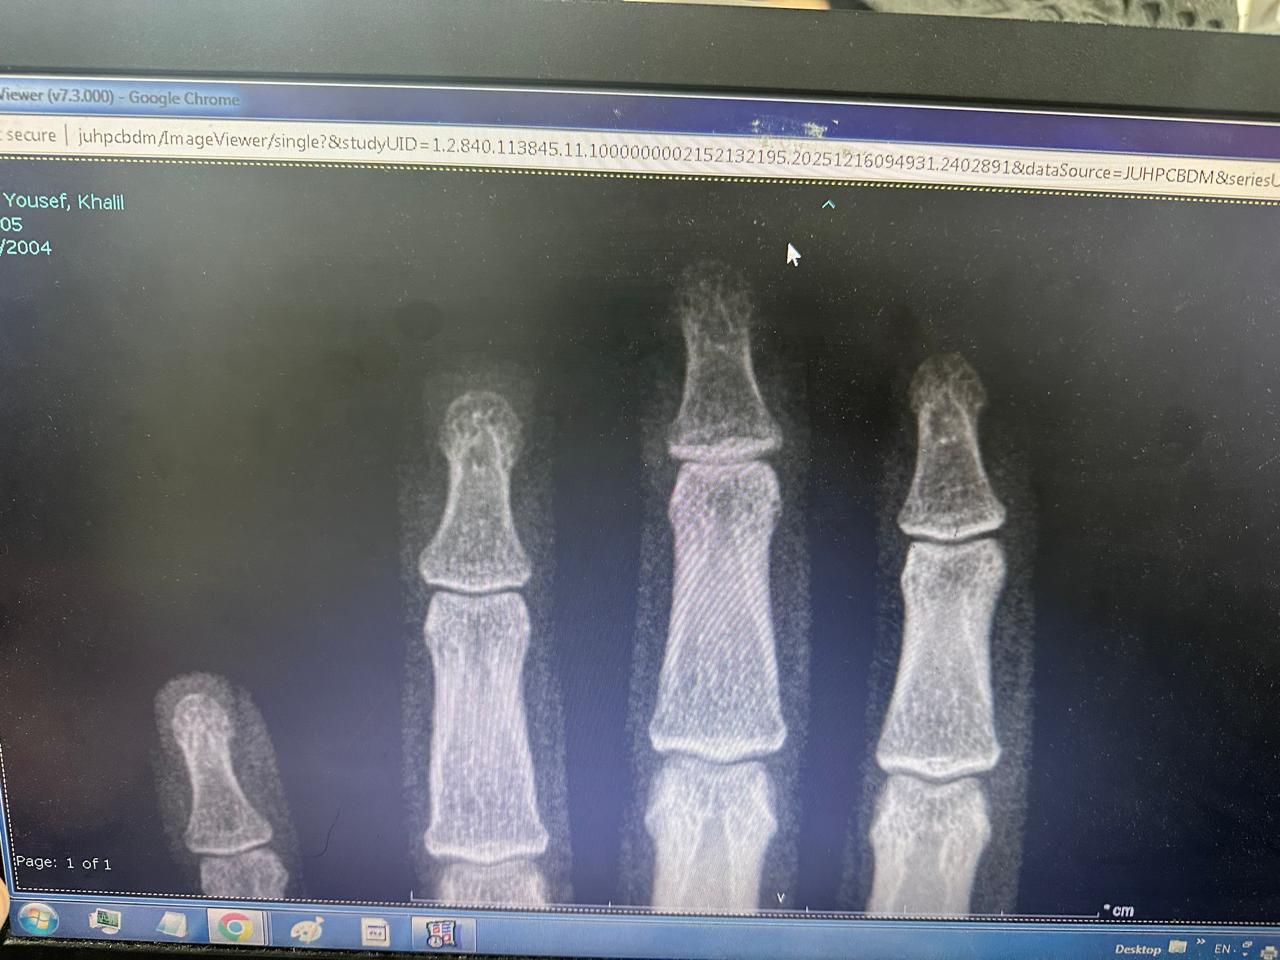

عظام قراءة الصورة لليد

- إصابة الأربطة: حتى لو لم يظهر التصوير وجود كسر، قد تكون هناك إصابة طفيفة في الأربطة.